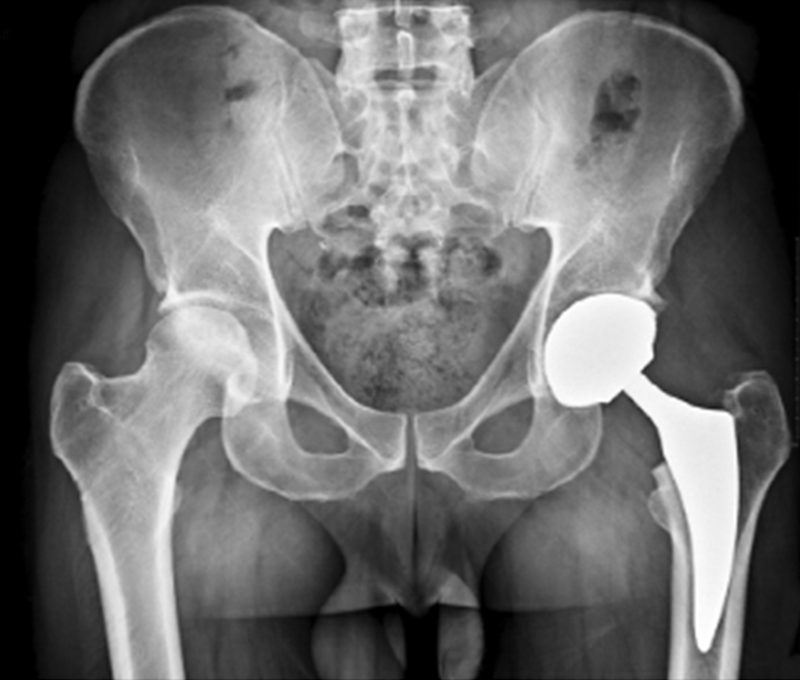

图1 该患者39岁,花园体力劳动者,因双髋疼痛求诊,发现双侧股骨头坏死、左股骨头塌陷。左侧进行全髋关节置换,无症状的右髋注射了干细胞。术后1年X线片显示,右股骨头保持圆形。